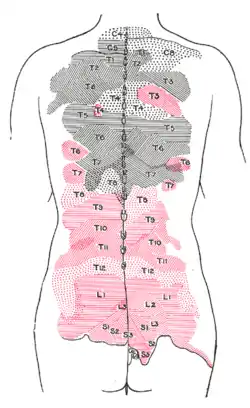

Areas of distribution of the cutaneous branches of the posterior divisions of the spinal nerves. The areas of the medial branches are in black, those of the lateral in red. | |

Diagram of the distribution of the cutaneous branches of the posterior divisions of the spinal nerves.

Diagram of the distribution of the cutaneous branches of the posterior divisions of the spinal nerves.